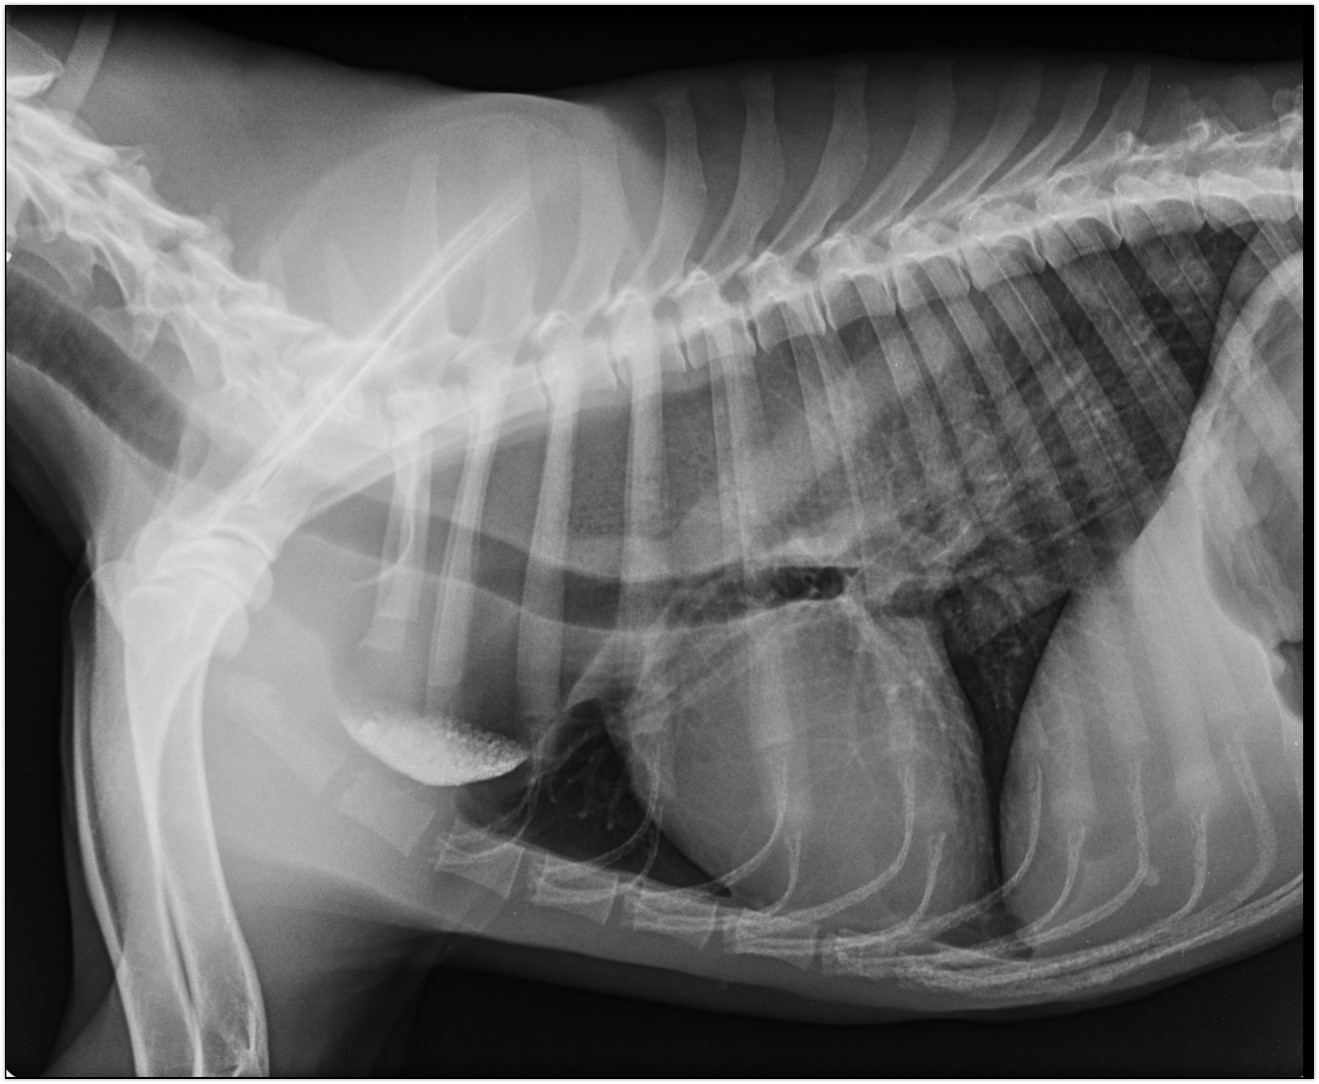

Consiste en tomar una imagen bidimensional de cualquier parte del cuerpo, aunque resulta de mayor utilidad para la evaluación del esqueleto axial y vías aéreas. En algunos casos se debe inyectar medios de contraste como el caso de vías urinarias, tracto digestivo y canal medular.

Contamos con equipos digitales lo cual permite la obtención de imágenes de forma directa y rápida. La técnica produce radiación ionizante por lo que la radioprotección tanto de los tutores como de los operarios es muy importante.